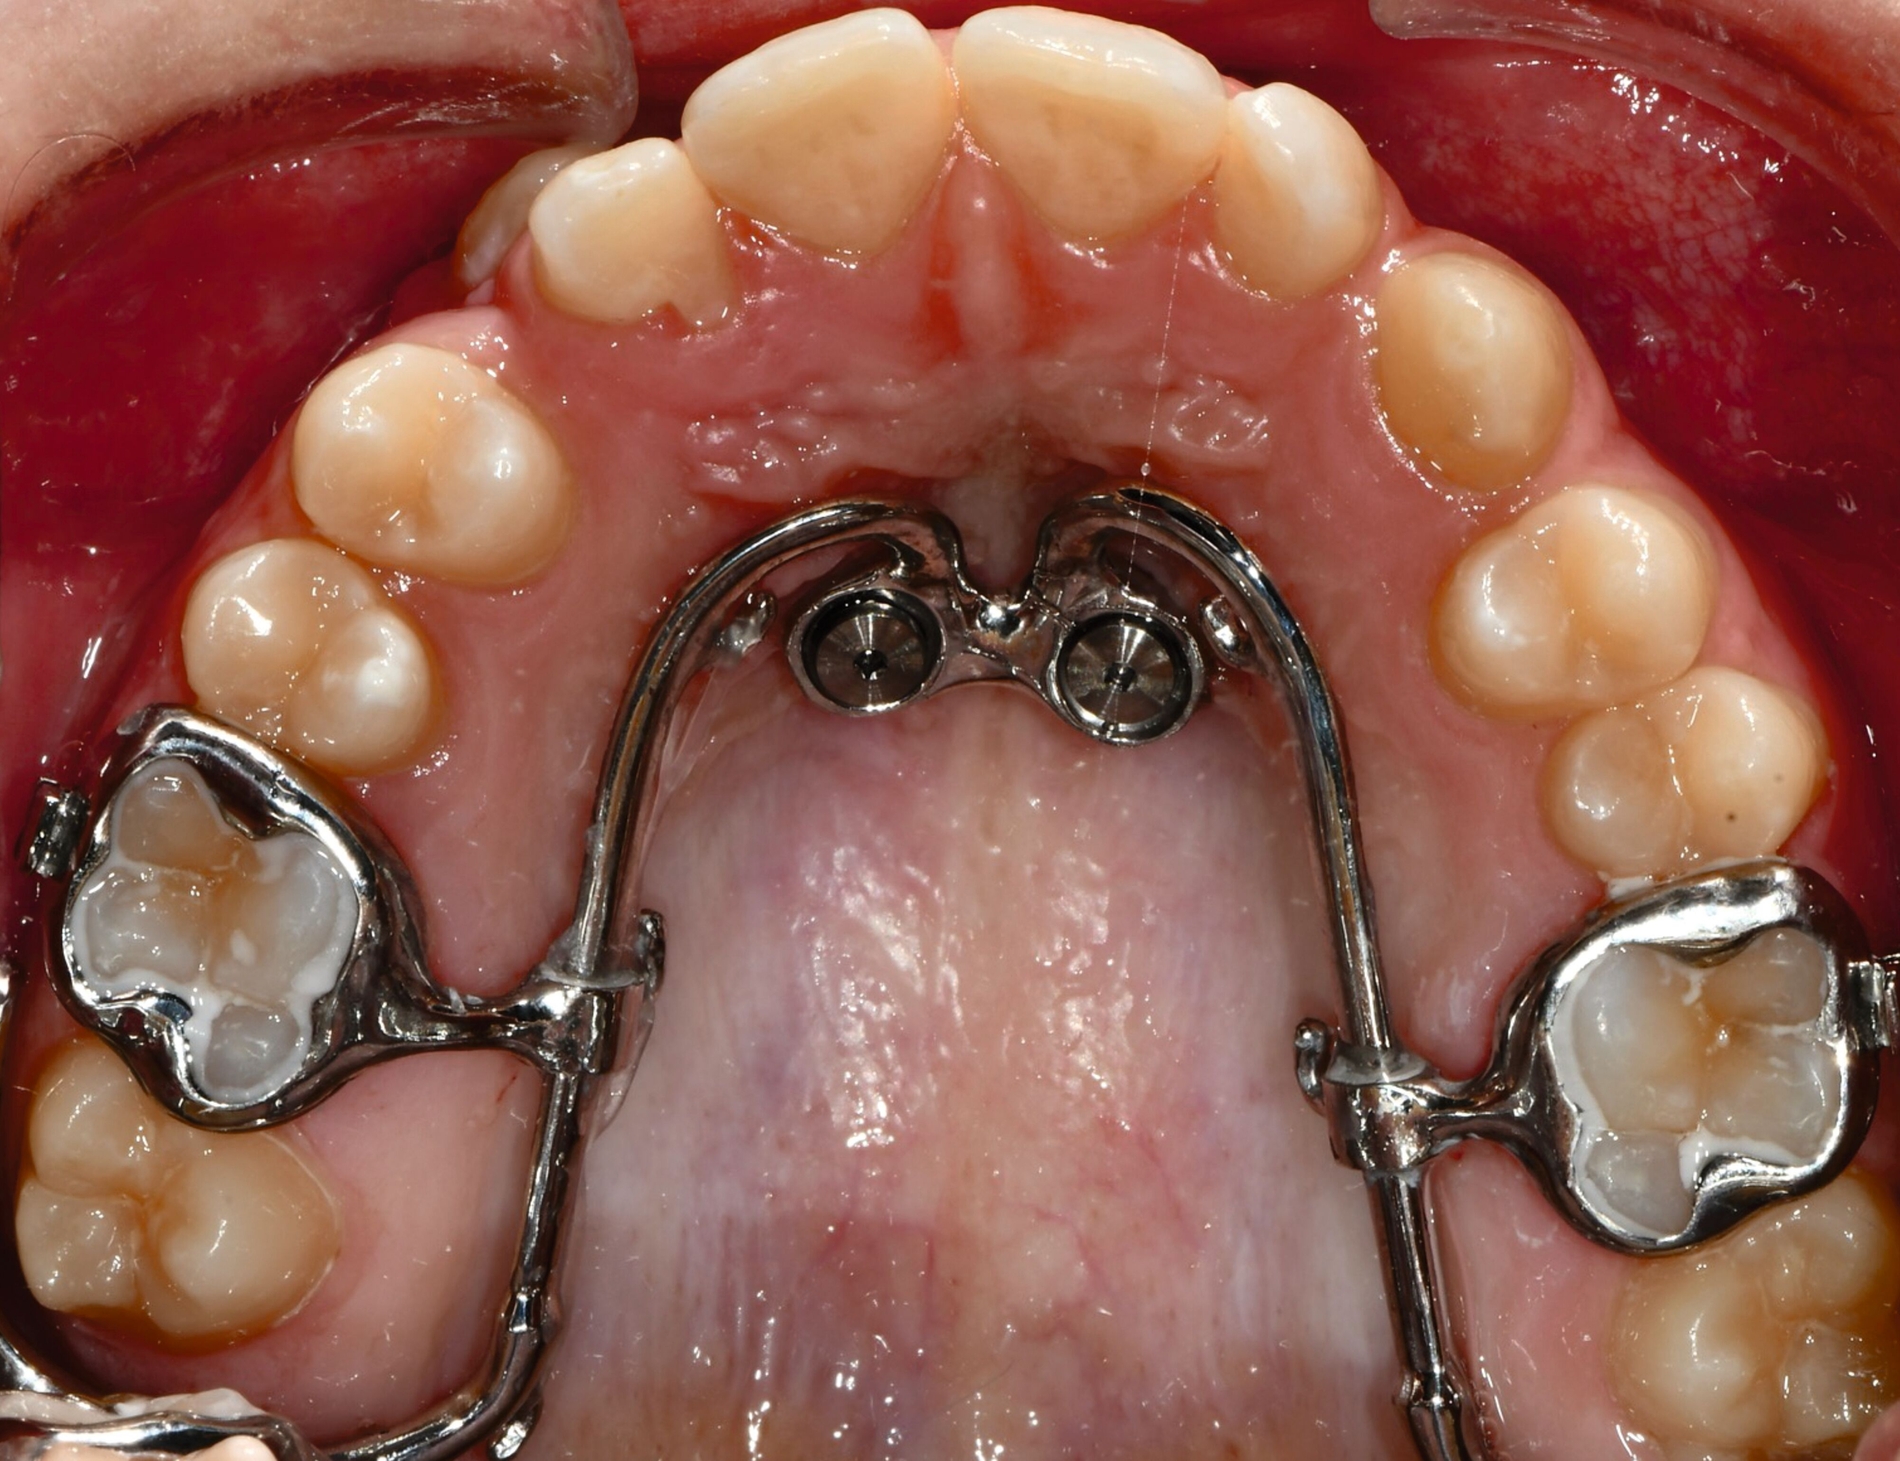

Anwendung findet der Metalldruck vor allem in der Herstellung skelettal verankerter Apparaturen, durch die reziproke Kräfte auf orthodontische Miniimplantate abgeleitet oder direkt skelettal aufgebracht werden können. Neben einer hohen Passgenauigkeit liegt der Vorteil vor allem in einer zielgerichteteren Therapie, die die anschließende oder zeitgleich durchgeführte Aligner- beziehungsweise Multibracket-Therapie verkürzt. Weiter können orthodontische Behandlungsaufgaben gelöst werden, die unter alleiniger Nutzung von Alignern beziehungsweise einer Multibracket-Apparatur deutlich limitiert wären. Beispiele beinhalten sogenannte „Mesialslider“ [Wilhelmy et al., 2022], „Distalslider“ [Graf et al., 2020] oder „Intrusionsapparaturen“.

Weiter erlauben hochindividuelle 3-D-gedruckte Designs die Therapie von skelettalen Fehlständen, beispielsweise in der Therapie defizitärer Maxillae [Pasqua et al., 2022; Bazargani et al., 2023; Ludwig et al., 2024] oder im Rahmen der nonoperativen oder postoperativen Prognathie-Behandlung [Hodecker et al., 2023]. Auch die Umsetzung skelettal verankerter Apparaturen mittels nichtmetallischer 3-D-Druckmaterialien findet in einzelnen Fällen Anwendung (Abbildung 3b). Zum Einbringen der Miniimplantate eignen sich sogenannte 3-D-gedruckte „Insertions-Guides“, die nach vorheriger digitaler Planung der Miniimplantat-Position, eine hochgenaue Insertion ermöglichen [Wilmes et al., 2022; Wilmes et al., 2022]. Die virtuelle Planung der Minischraubeninsertion ermöglicht eine sichere und nachvollziehbare Evaluation sämtlicher relevanter Gewebe, um die ohnehin geringen Risiken weiter zu minimieren. Zusätzlich kann man die Biomechanik der digital geplanten kieferorthopädischen Apparatur ideal koordinieren und – wenn man möchte – die Minischrauben und die Apparatur in einer Sitzung einsetzen.